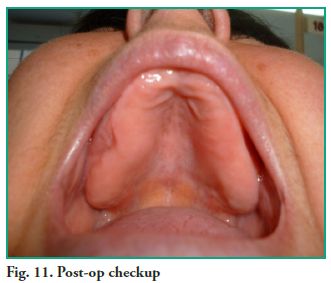

For the postoperative phase, the patient was prescribed Amoxicillin 500 mg every 8 hours for 10 days and Ibuprofen 400 mg every 6 hours for a period of 48 to 72 hours, as analgesic and anti-inflammatory agent. Since no counter opening was made in the inferior meatus, she was prescribed vasoconstrictive nasal drops to keep the ostium patent, for the purpose of facilitating drainage until discharge. The suture was removed ten days later, and the patient’s progress was checked every week for 2 months (Fig. 11).

For the postoperative phase, the patient was prescribed Amoxicillin 500 mg every 8 hours for 10 days and Ibuprofen 400 mg every 6 hours for a period of 48 to 72 hours, as analgesic and anti-inflammatory agent. Since no counter opening was made in the inferior meatus, she was prescribed vasoconstrictive nasal drops to keep the ostium patent, for the purpose of facilitating drainage until discharge. The suture was removed ten days later, and the patient’s progress was checked every week for 2 months (Fig. 11).